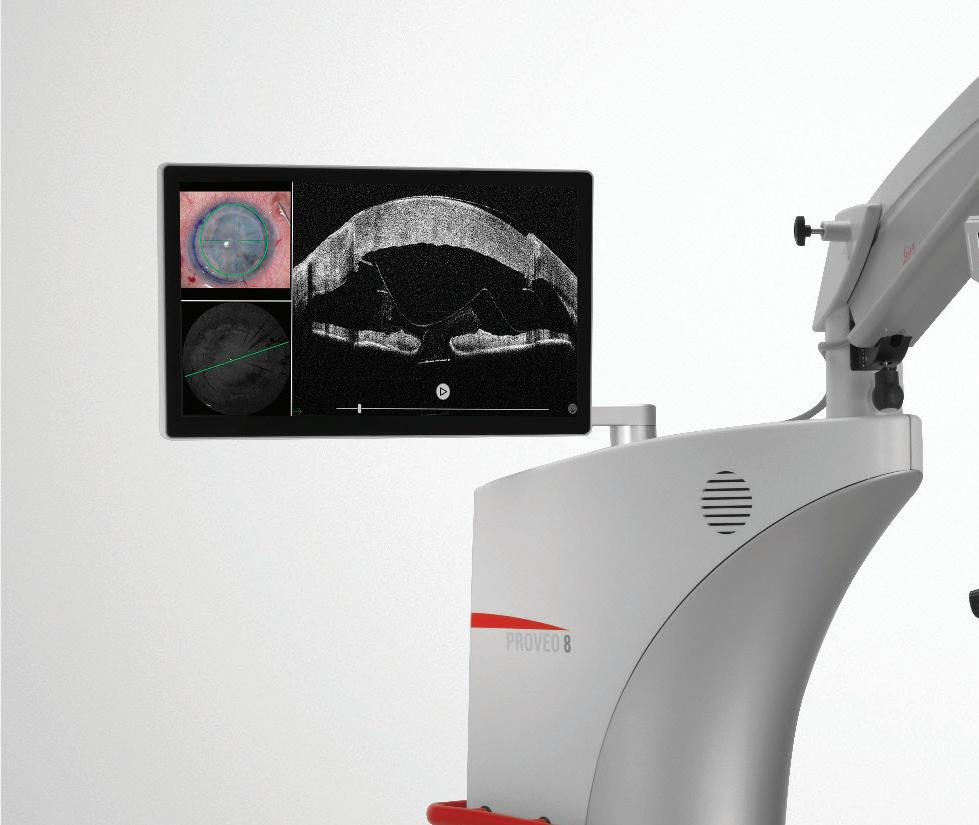

Proveo 8

Η νέα πρόταση που επαναπροσδιορίζει την κορυφαία κατηγορία.

Ξεπερνάει τα όρια της οπτικής, προσφέροντας 40% αυξηµένο

βάθος πεδίου, χάρη στο επαναταστικό σύστηµα Fusion Optics.

Νέος τετραπλός οµοαξονικός φωτισµός µε 2 Led για βέλτιστο Red reflex.

Compact κατασκευή, όλα τα περιφερειακά είναι πλήρως

ενσωµατωµένα στην εργονοµική βάση µικρών διαστάσεων.

Ενσωµατωµένη σχισµοειδής λυχνία.

Πλήρης έλεγχος του Biom 5c από τον ίδιο ασύρµατο

ποδοδιακόπτη και λειτουργία combined focus για σταθερή

απόσταση από τον ασθενή.

Αναβαθµίζεται και δέχεται ενσωµατωµένα τεχνολογίες

αιχµής όπως, markerless καθοδήγηση για τοποθέτηση

τορικών ενδοφακών, διεγχειρητικό OCT και προβολή

δεδοµένων στους προσοφθάλµιους.

∆ιεγχειρητικό OCT Leica Enfocus

Προσθίου & Οπισθίου Ηµιµορίου

Παραδίδεται είτε ενσωµατωµένο εξαρχής µε το µικροσκόπιο Proveo 8, είτε ενσωµατώνεται πλήρως µελλοντικά, ως αναβάθµιση.

• Ανάλυση έως 4µm

• Βάθος έως 11mm

• 36.000 σαρώσεις το δευτερόλεπτο

• Πρωτοποριακός σχεδιασµός µε ανεξάρτητο beam path για βέλτιστη ποιότητα εικόνας

• ∆υνατότητα ανεξάρτητης ρύθµισης της θέσης και του βάθους σάρωσης.

• Λογισµικό µετρήσεων απόστασης µεταξύ σηµείων

• Αυτόµατη αναγνώριση σηµείου εστίασης

Η Εταιρεία Leica είναι πρωτοπόρος

και σε άλλες ειδικότητες, όπως ΝΧ, ΩΡΛ, Πλαστικής & Γενικής Χειρουργικής

• ∆υνατότητα προβολής εικόνας και απευθείας στους προσοφθάλµιους του χειρουργού.

• Αναβαθµίσιµο σε νέες λειτουργίες